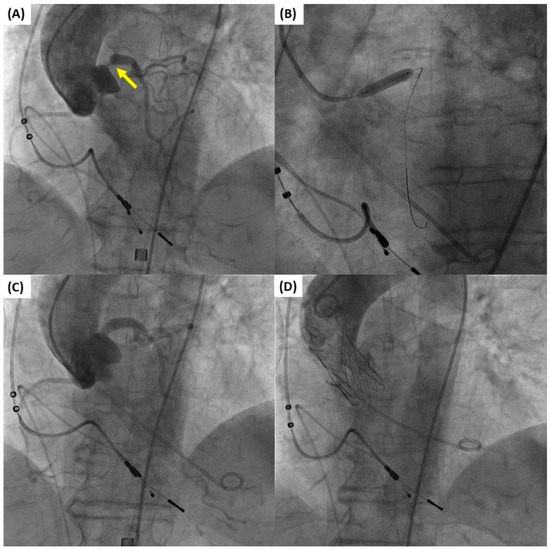

A number of studies have supported the safety and feasibility of TAVI with concurrent PCI (Figure 2). Wenaweser et al. demonstrated that in a specific group of patients, revascularization by PCI can be safely performed alongside TAVI, either as a staged or simultaneous procedure [44]. Similarly, Conradi et al. presented their findings on the feasibility and safety of staged or single-stage TAVI and PCI in this high-risk patient population [45]. In addition, Pasic et al. demonstrated that the combined elective PCI and TAVI procedure using a single-stage technique is both possible and secure [46]. Conversely, Singh et al. demonstrated that patients who received PCI concurrently with TAVI experienced elevated rates of death while still in the hospital [47]. Similar findings were reported by Griese et. al, who found that performing contemporaneous PCI with TAVI in specific elderly individuals resulted in higher rates of early and late mortality [48]. While this approach has the benefit of avoiding multiple procedures and potentially lowering the risks associated with obtaining vascular access at different times, it does result in a higher volume of contrast media being used during the TAVI procedure. This could potentially raise the risk of contrast-induced nephropathy, especially in patients with complex CAD.

Figure 2. Simultaneous percutaneous coronary intervention (PCI) of the left main and transcatheter aortic valve implantation (TAVI) in an 80-year-old female patient with severe aortic stenosis and obstructive left main coronary artery disease (arrow). (A) Baseline aortogram showing aortic valve stenosis and critical stenosis of the left main coronary artery necessitating revascularization. (B) Stent implantation at the left main ostium. (C) Aortogram after PCI. (D) Aortogram after Accurate Neo2 (Boston Scientific, Natick, MA, USA) transcatheter aortic valve implantation.